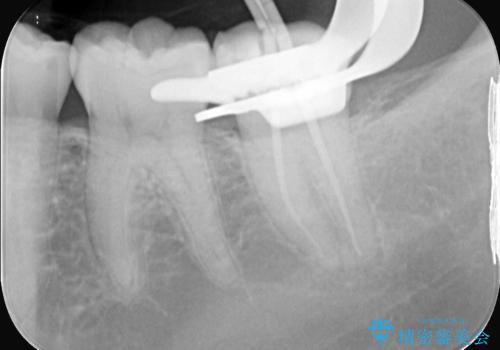

- 定期検診にて虫歯が見つかり、セラミックインレーに治療を行っております。

e-max プレスインレーにて修復治療を行っているため適合性及び審美性の高い治療を行うことができます